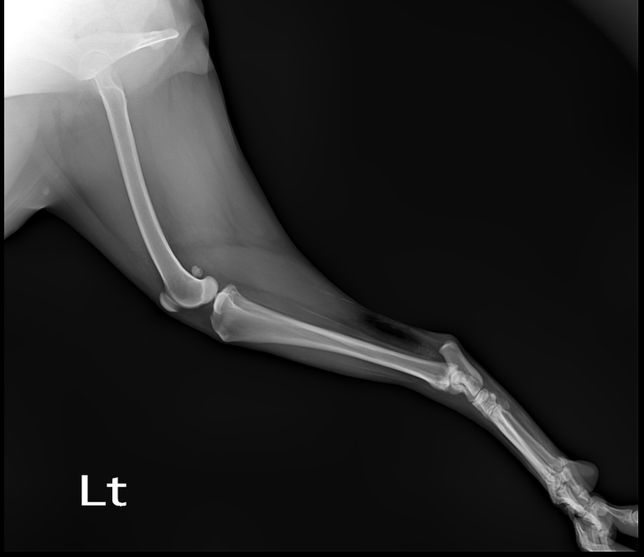

Q. 강아지 엑스레이상 문제 없는데 발이 왜 이상할까요?계단 오르다 발을 헛딛고 못 딛어서 엑스레이찍어 봤는데 엑스레이상 문제는 없다고 하셨어요 하지만 현재 발 모양이 이상해서요 인대 문제라고 하셨는데 인대로 인한 발 모양이 변했다면 언제쯤 다시 돌아 올까요? 삼일째 되는 날 발을 중간중간 딛기는 하는데..너무 걱정되네요 다른 의견도 듣고 싶어 질문 합니다.다친발 사진정상 발 사진

• 강아지 엑스레이상 문제 없는데 발이 왜 이상할까요?의 0번 째 이미지

• 강아지 엑스레이상 문제 없는데 발이 왜 이상할까요?의 1번 째 이미지

• 강아지 엑스레이상 문제 없는데 발이 왜 이상할까요?의 2번 째 이미지

• 강아지 엑스레이상 문제 없는데 발이 왜 이상할까요?의 3번 째 이미지